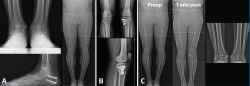

La región diafisaria de la tibia también puede presentar una desaxación como consecuencia de una consolidación viciosa de una fractura de tibia. En este escenario, la artropatía del tobillo puede mejorar de manera muy llamativa con la corrección de la deformidad proximal (Figura 2).

Figura 2. Paciente con consolidación viciosa tras fractura diafisaria de tibia tratada ortopédicamente y dolor incapacitante en el tobillo ipsilateral. A: las telerradiografías muestran una deformidad en valgo; B: la deformidad es multiplanar y la radiografía en proyección lateral nos muestra un recurvatum importante; C: se realizó una osteotomía en el CORA (center of rotation of angulation) con cierre medial y posterior, corrigiendo además la alteración rotacional; D: la fijación se consiguió con un clavo intramedular. Aunque el tobillo no estaba radiológicamente “sano”, la mejoría de la paciente fue muy notable y no ha precisado (5 años después de la corrección) cirugía adicional en el tobillo.